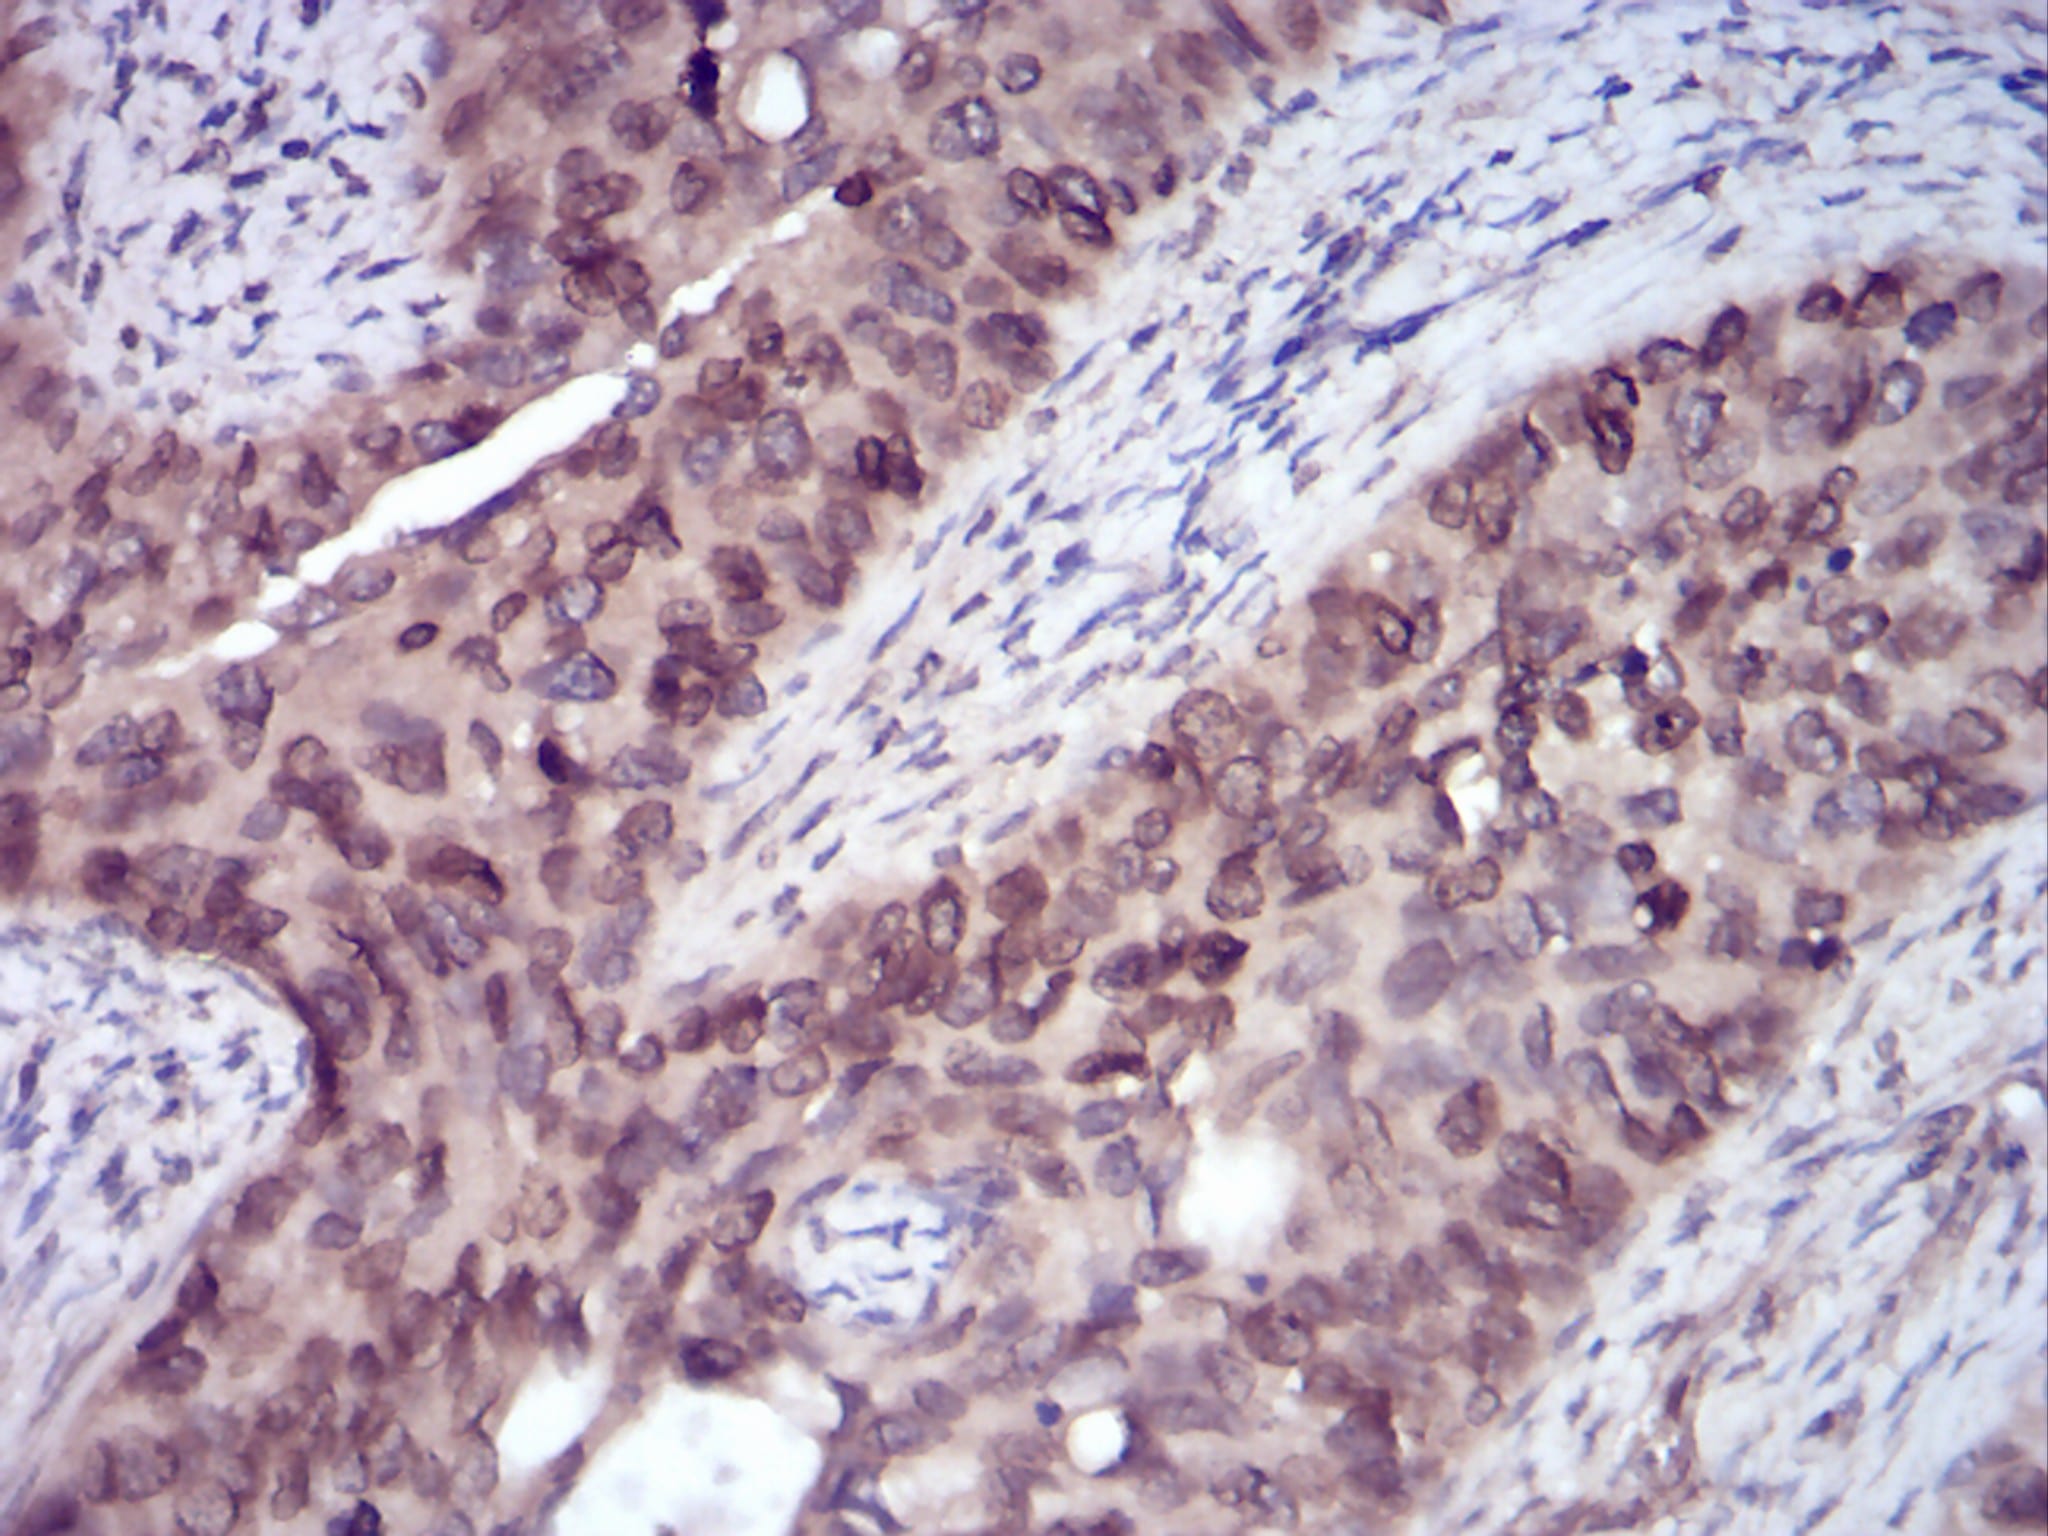

分类: 科研抗体货号: 30755别名: HER4; ALS19; p180erbB4应用: IHC,FCM反应种属: Human